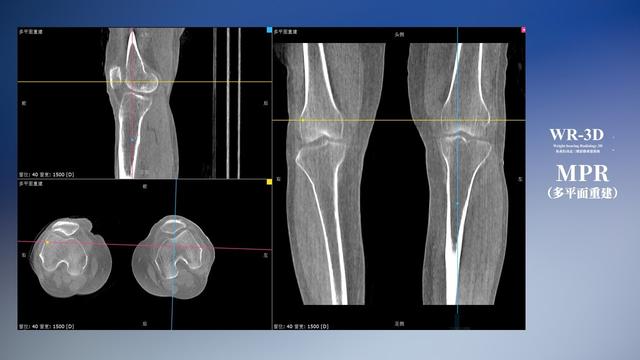

在负重位状态下,数字化X线三维扫描与重建,能够更好的呈现受检者关节受力改变的状态。ty8天游平台登录科技创新的WR-3D动态三维影像重建系统,通过数字化X线摄影完成三维扫描并重建三维影像信息,包括断层图像重建、MPR多平面重建、MIP重建以及VR体绘制。其扫描时间短,剂量相较于CT设备大幅缩减,同时成本更低,在临床诊断以及医疗方案制定中具有极大的价值意义。而相较于普通平片下的负重位扫描,负重位动态三维影像重建技术能够避免二维状态下的组织结构重叠、密度分辨率不足、组织解剖结构难以分辨等问题。WR-3D支持多角度的三维观察,能全面的呈现被检查部位在多个角度下的三维影像信息,极大的降低了二维负重位检查带来的漏诊率。

ty8天游平台登录科技WR-3D负重位动态三维影像重建图像